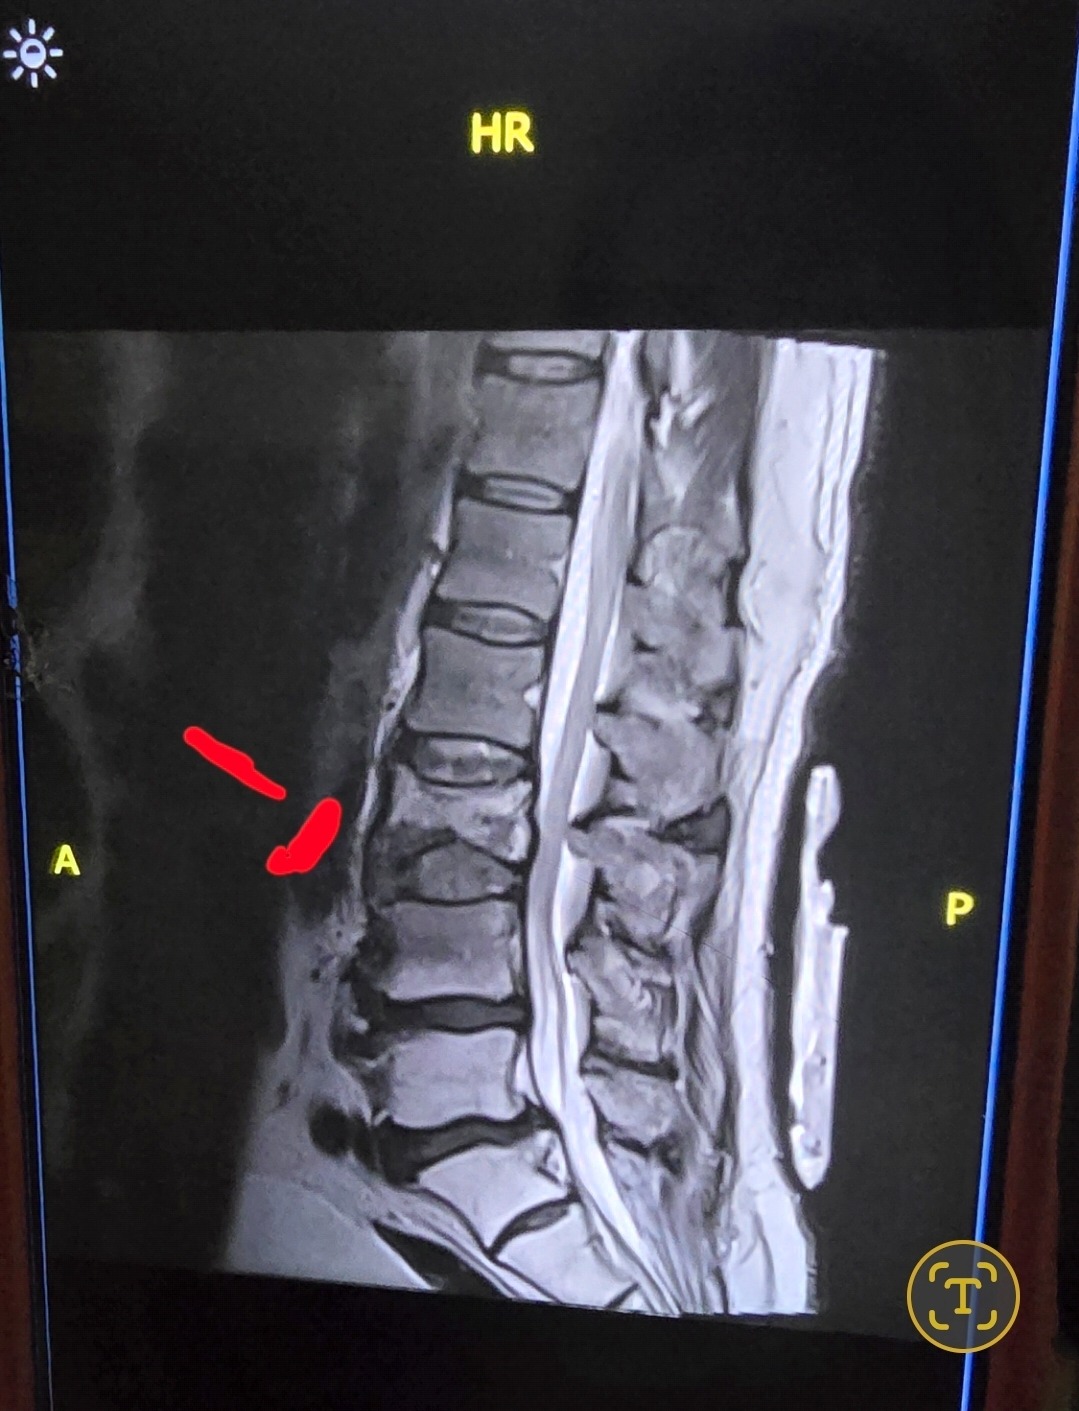

El día 20 de marzo, cuando se encontraba trabajando como camionero, sufrió una horrible caída en la que se le afectaron varios discos, y una vértebra se partió. Fue trasladado al AdventHealth de Zephyrhills, donde decidieron llevarlo a cirugía, en la cual le pusieron placas y varios tornillos debido a la magnitud de la fractura.

On March 20, while working as a truck driver, he suffered a terrible fall that affected several discs, and one of his vertebrae was fractured. He was taken to AdventHealth in Zephyrhills, where doctors decided to perform surgery. Due to the severity of the fracture, they placed plates and several screws.